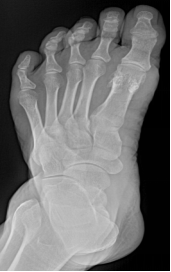

多指畸形

手足短骨解剖及常见疾病的影像学表现